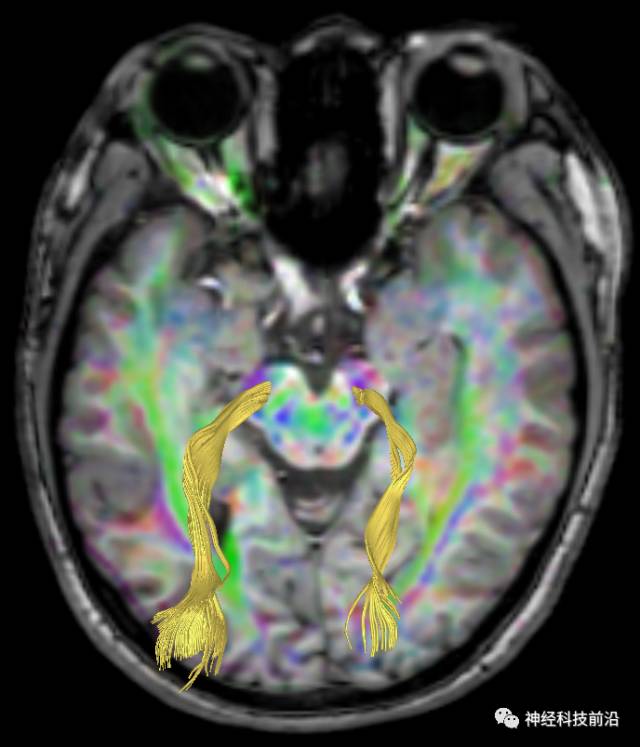

皮质脑桥束与脑干高信号(黄色)纤维束

脑干内高信号为一近环形纤维束,其作用尚待研究。

终上所述:脑干高信号为一近环形纤维束,内囊后肢高信号为皮质脑桥束,皮质脊髓束在中脑位置略靠后。高信号位于中脑前缘,是皮质脑桥束的位置所在,另外有部分桥连纤维。